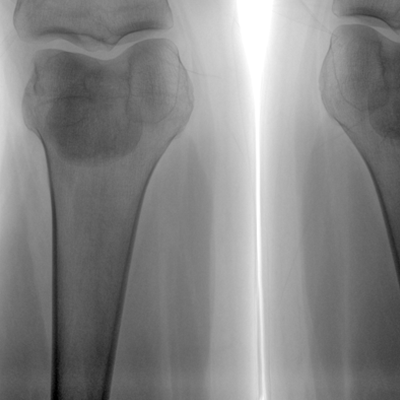

大尺寸液晶顯示器,圖像顯示清晰細膩;顯示器可大角度旋轉,滿足臨床多角度觀察圖像的需要。

在球管和平板探測器兩端,分別加裝了激光定位系統,滿足不同擺位無射線下的定位需求,降低醫患輻射劑量的同時,提高臨床工作效率。

具備束光器預覽功能,可以在無射線狀態下,實現曝光范圍大小的調節;大幅減少臨床反復曝光帶來的射線輻射;并自動調整圖像興趣區大小與位置,使自動模式更準確。